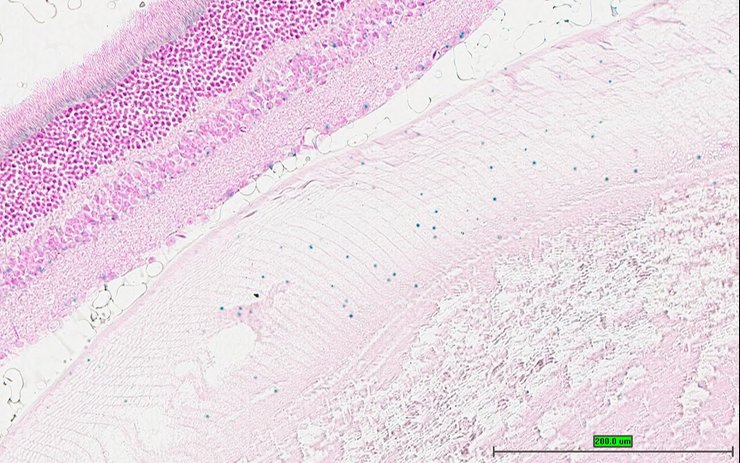

TS28: eye Present UC Davis_1885961

Specimen UC Davis_1885962: postnatal adult; Ubxn2atm1b(EUCOMM)Hmgu/Ubxn2a+ (more )

Structure Level Pattern Image Note

TS28: eye Present UC Davis_1885962

Specimen UC Davis_1885963: postnatal adult; Ubxn2atm1b(EUCOMM)Hmgu/Ubxn2a+ (more )

TS28: eye Present UC Davis_1885963

TS28: eye Present UC Davis_1886018

Specimen UC Davis_1886019: postnatal adult; Ubxn2atm1b(EUCOMM)Hmgu/Ubxn2a+ (more )

TS28: eye Present UC Davis_1886019